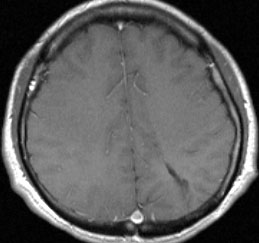

20代の男性の神経細胞腫です。側脳室の中のとても大きな腫瘍です。上段はガドリニウムという造影剤を入れた時のMRIです。下段の中央はCTですが,石灰化が見られます。脳外科の先生には,この脳室内腫瘍は一見transcallosal approach(経脳梁到達法)という手術で取れるように見えるかもしれませんが,そうではなくて,脳室の壁とくに上壁と側壁にくっついているのでなかなか取れません。この患者さんの場合は右の頭頂葉というところからtranscortical approach(経皮質到達法)で全摘出しました。後遺症もなく再発もなく術後10年が過ぎています。全部とれれば治ってしまう腫瘍です。

手術後の画像です。脳神経外科の先生は手術根 surgical track に注目して下さい,左頭頂葉皮質切開 transcortical approachで手術を行っています。このルートでは全く手術後の神経脱落症状が出ませんでした。central neurocytomaの手術方法は,上記に加えて前頭葉皮質切開でまっすぐ前角に入る方法と経脳梁法 transcallosal approachがあります。経脳梁法は限られた小さめの腫瘍にしか応用できません。anterior callosal approach以外ではdisconnection syndromeが出るからです。central neurocytomaは脳室の壁にベトベトくっつくし,anterior callosal approachでは脳室壁の観察はかなり限られるからです。大きなものでは必ず経皮質法を選択して下さい。